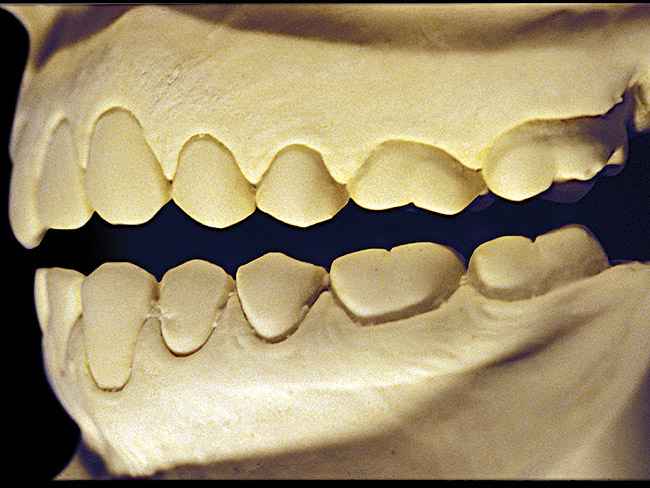

The patient shown in Figure 3 and Figure 4 exhibited severe NCLTS from bruxism. Examination of the casts indicated that the NCLTS was progressively greater toward the anterior teeth. Cupping and cratering was not present because there was no secondary cause. Figure 5 and Figure 6 detail another bruxism patient, but to a lesser degree and one with cupping/cratering caused by toothpaste. The cups or craters were not caused from bruxism because the teeth could not touch the bottom of the invaginations. In both featured patients, upon hand-articulating the casts, the NCLTS facets matched up and the diagnosis of bruxism was confirmed.

Figure 4  Advanced NCLTS from bruxism, maxillary arch.

Figure 4